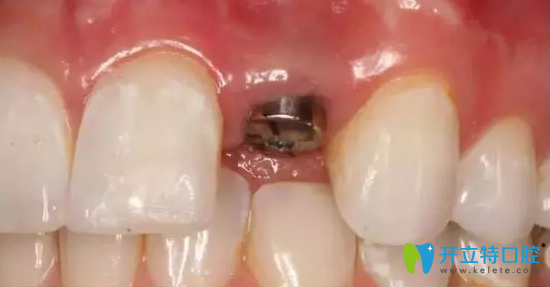

在北京齒康口腔剛植入人工種植體

這個過程打了麻藥,是不疼的。醫(yī)生說3—6個月會恢復(fù)好,到時候再裝基臺和牙冠。種植體植入后,我就回家了,期間和醫(yī)生經(jīng)常微信聯(lián)系,看看我有沒有疼痛和腫脹。